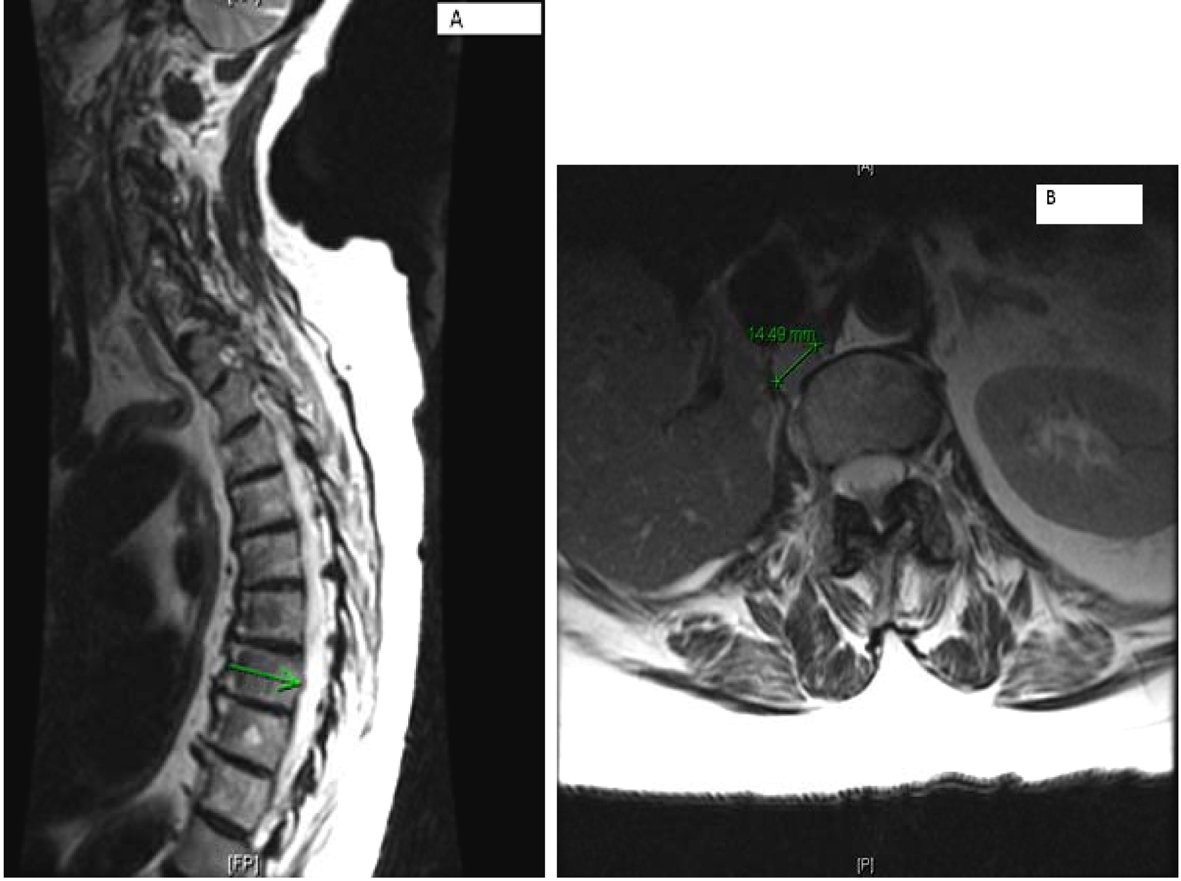

MRI of the spine confirmed bilateral iliac bone metastasis, T-10 diffuse infiltration of metastasis, retroperitoneal lymph nodes and several nodules along the crus of the right diaphragm (Fig. 4). Patient was started on denosumab and zoledronic acid, and she received 10 fractions of radiotherapy to her right hip.

![]() Click for large image | Figure 4. (A) Multilevel-multifocal osseous metastases particularly within thoracolumbar spine with slight epidural extension at T-7 and mild epidural disease at T-10 without cord compression. (B) Right retrocrural/paraspinal metastasis is seen at T-12 and L-1 level measuring about 1.5 cm. |